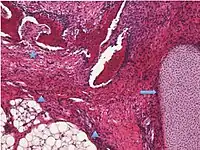

| Sex cord-stromal tumor: pure stromal tumors, pure sex cord tumors and mixed sex cord-stromal tumors | Ovarian fibroma | 1.5% | 0% | Spindle-shaped fibroblastic cells and abundant collagen.[19] | ![]() | ![]() |